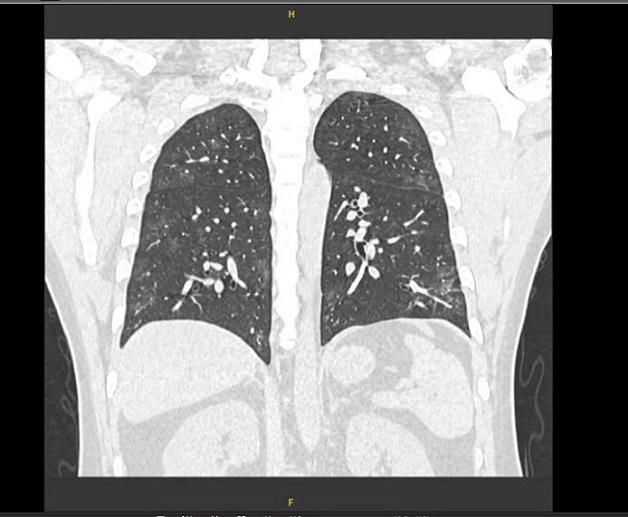

HÌnh ảnh chụp cắt lớp phổi phát hiện tổn thường dạng kính mờ và xơ hóa phổi trên phim chụp CT.

Hình ảnh chụp cắt lớp vi tính phổi của BN đến khám hậu COVID-19 tại Thu Cúc TCI.